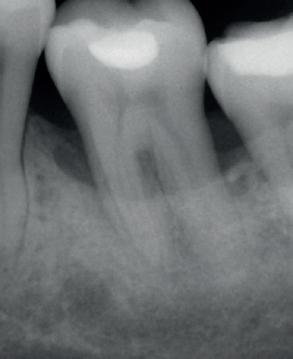

Elektrolytische Reinigung von Zahnimplantaten

Periimplantäre Erkrankungen betreffen immer mehr Patient*innen, da die Zahl der gesetzten Implantate weltweit exponentiell zunimmt.(1) Aus diesem Grund ist in den letzten Jahren auch die Behandlung von biologischen Komplikationen und vor allem die Behandlung einer Periimplantitis stärker in den Fokus gerückt.

Ein wesentlicher, jedoch schwieriger Schritt dabei ist die gründliche Reinigung der Implantatoberfläche. Unter den bisher in der Literatur beschriebenen Methoden im Rahmen der nicht-chirurgischen und chirurgischen Dekontamination erwies sich keine als eindeutig überlegen. (2,3)